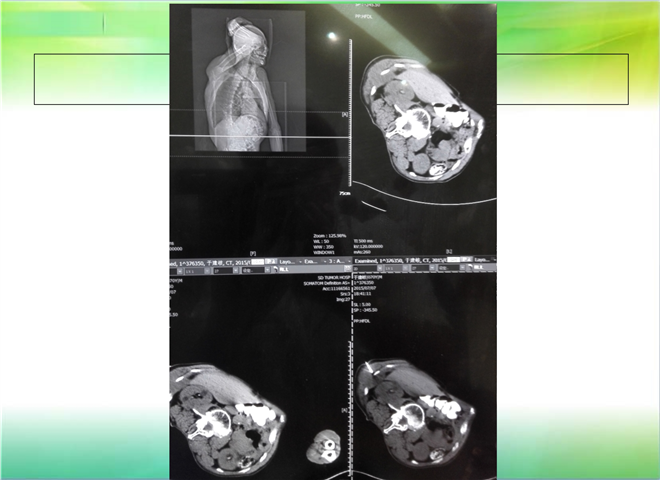

CT引导下穿刺活检术